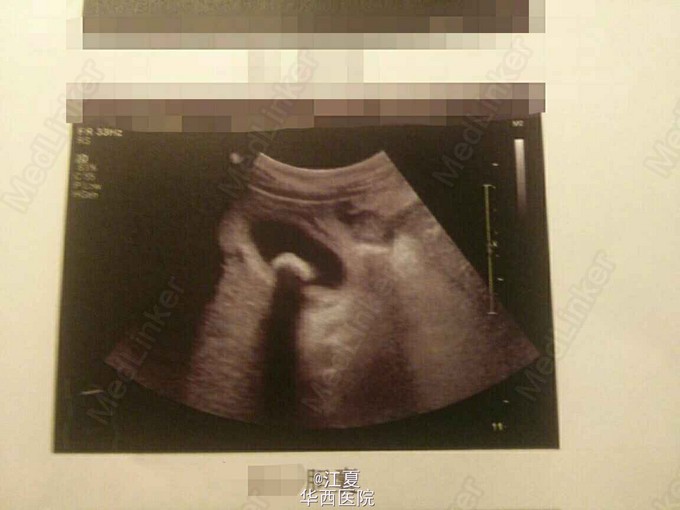

超声下的胆囊结石

胆囊结石

胆囊壁增厚,囊内可见高回声团块,伴后方声影。